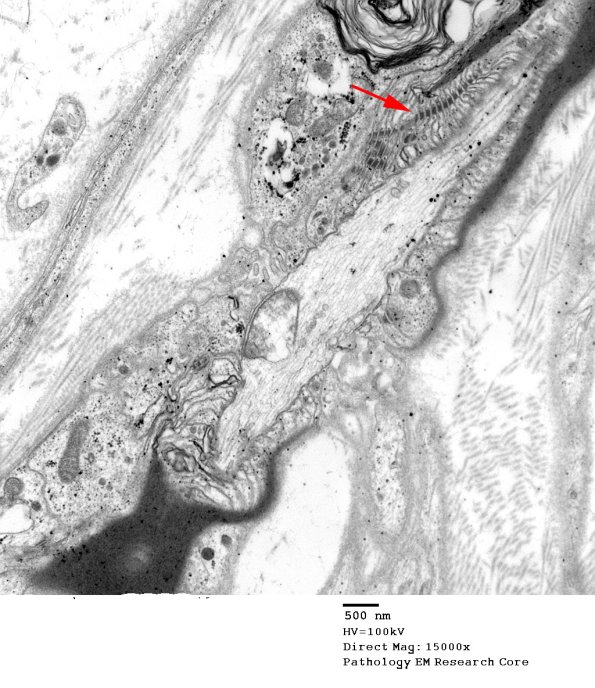

15A1,2 Junctional elements (arrow,) stabilize the paranodal loops. (electron micrographs)